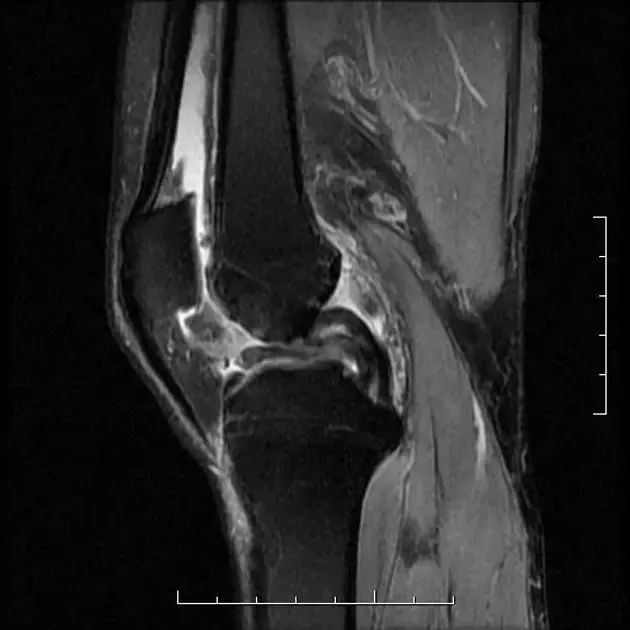

众所周知,每个膝关节后交叉韧带只有一条,下图为解剖示意图。

图1 膝关节后交叉韧带模拟图和膝关节矢状位 MRI T2WI 图像,红色箭头所指为正常后交叉韧带